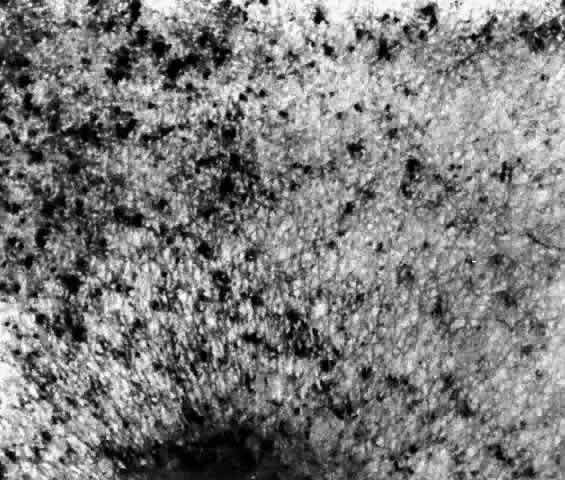

These deposits are strongly birefringent, and striking macular birefringence may be readily visualized in sections of the retina (Fig. 5) even in the unstained state as well as when lightly stained with cresyl violet or sudanophilic dyes.8 Loss of the ganglion cells and atrophy of the optic nerve, which is also evident, are accompanied by a thinning of the nerve fiber layer.

Fig. 5. Birefringence of ganglion cell layer of macula in Tay-Sachs disease. Frozen section, cresyl violet stain, photographed between crossed polaroids (x 80). (Cogan DG, Kuwabara T: The sphingolipidoses and the eye. Arch Ophthalmol 79:437, 1968. Copyright © 1968, American Medical Association)